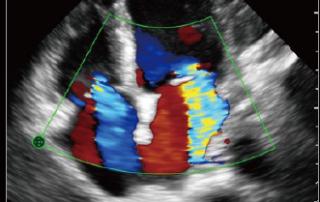

TE Air